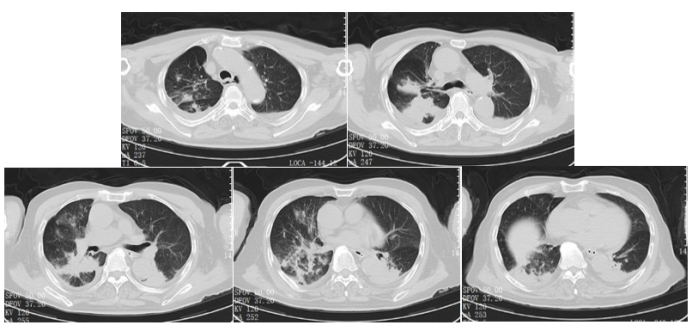

根据病原回报结果,1月13日停用美罗培南因伏立康唑血药浓度偏高且肾功能恶化,将原研伏立康唑针改为口服伏立康唑片0.2 q12h;加用更昔洛韦针0.2 5 q12h针对人类α疱疹病毒1型);针对纹带棒杆菌加用利奈唑胺针0.6 q12h;1月17日患者复查肺部CT提示双肺感染面积较前明显增加,少许胸腔积液并伴有肺不张5

图片

5  复查胸部CT(2025-01-17